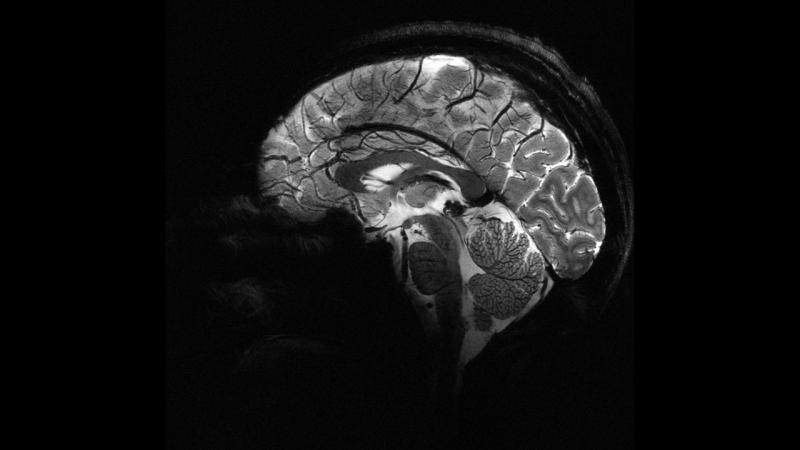

Во время эксперимента к лобной и теменной областям, расположенным в передней и задней частях мозга, применялся электрический ток. Было замечено, что когда эти две области стимулировались одновременно, участники делили больше денег.

Это исследование основано на предыдущих исследованиях, в которых отслеживалась мозговая активность участников во время игры в разделение денег. Предыдущее исследование показало, что когда делится больше денег, области мозга, отвечающие за принятие решений и эмпатию, «общаются» с одинаковой частотой. Новый эксперимент доказал, что внешнее вмешательство может вызвать общение между этими областями и заставить людей принимать более самоотверженные решения.

Доктор Цзе Ху из исследовательской группы сказал, что самым новым аспектом исследования является выявление причинно-следственной связи. Ху подчеркнул, что изменение коммуникации в определенной мозговой сети с помощью целенаправленной нехирургической стимуляции напрямую влияет на то, как люди уравновешивают свои интересы с интересами других.